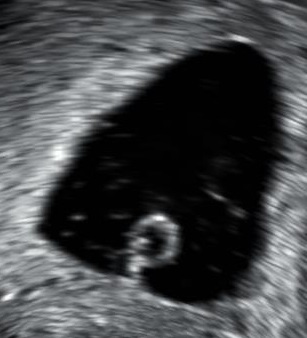

Anembryonic gestation.jpg

An ultrasound showing a gestational sac containing a yolk sac but no embryo

An anembryonic pregnancy (also called an "empty sac" or "blighted ovum") is a condition where the gestational sac develops normally, while the embryonic part of the pregnancy is either absent or stops growing very early. This accounts for approximately half of miscarriages. All other miscarriages are classified as embryonic miscarriages, meaning that there is an embryo present in the gestational sac. Half of embryonic miscarriages have aneuploidy (an abnormal number of chromosomes).[50]